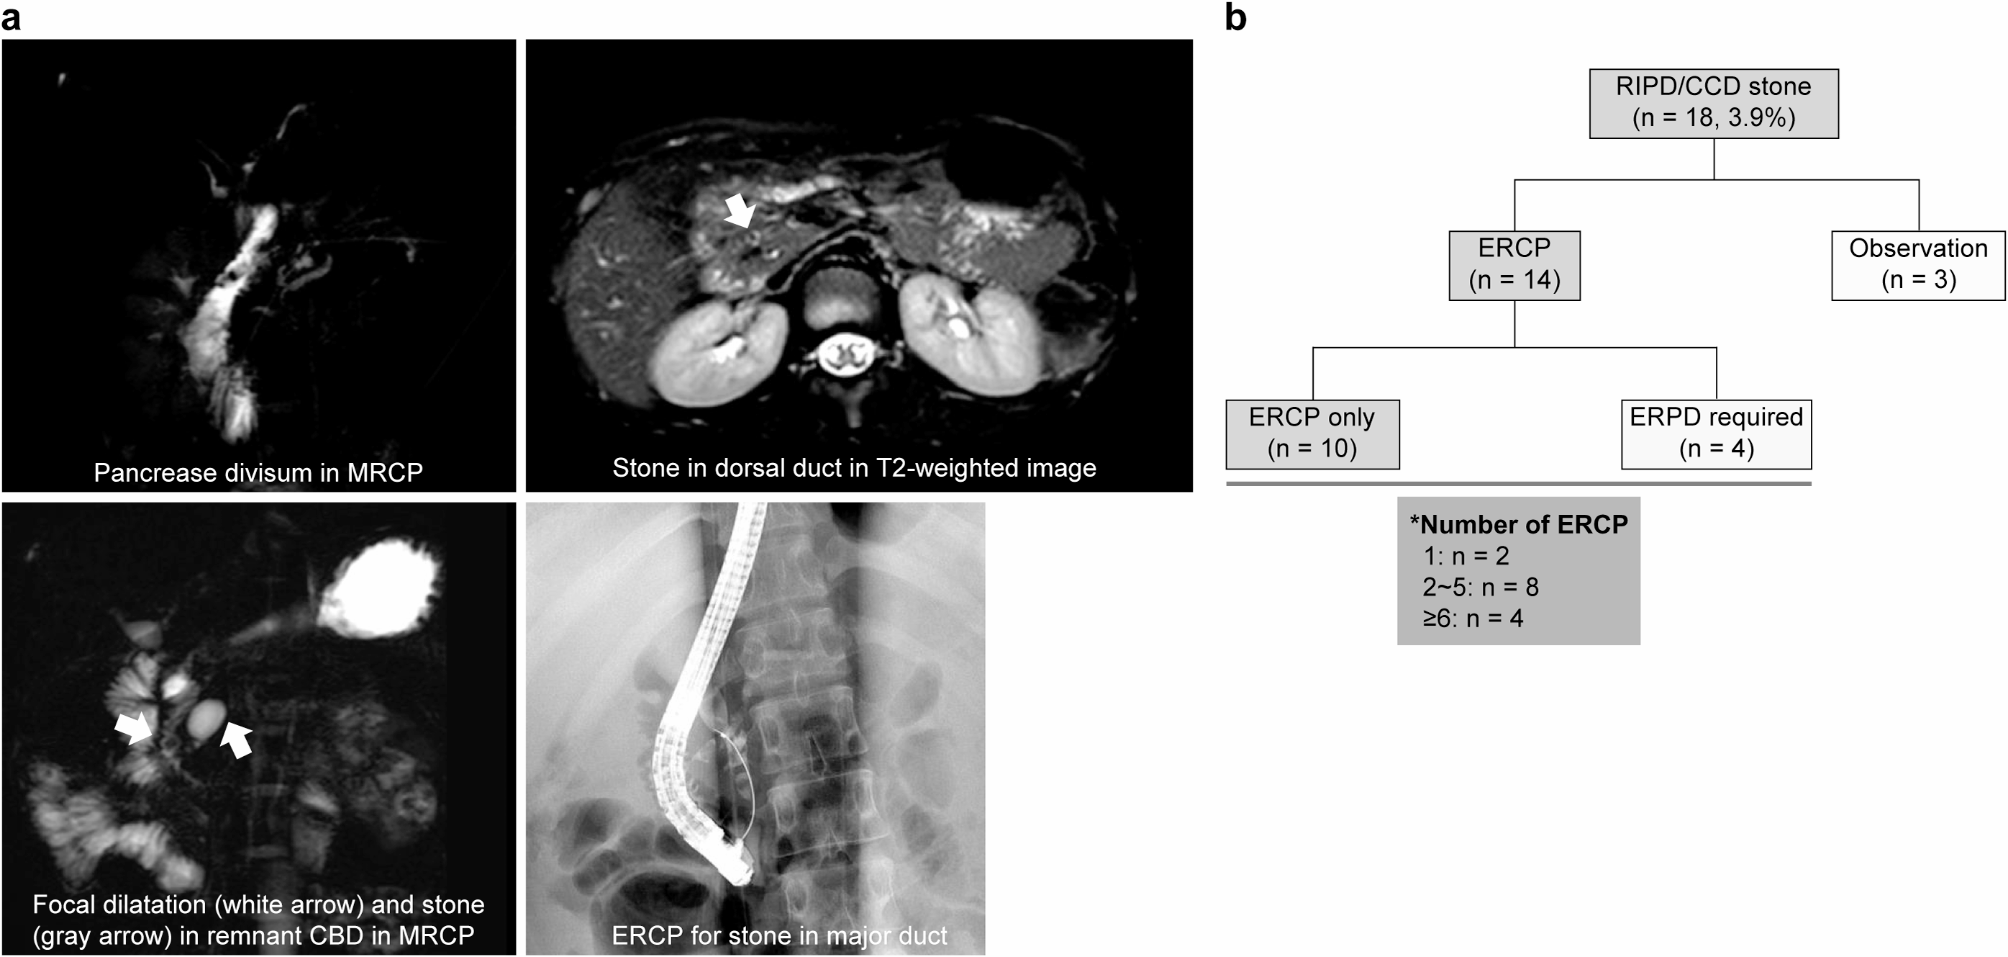

Choledocholithiasis in RIPD/CCD. (a) Each image shows the following: pancreas divisum as seen on the 2D T2 thick-slab turbo spin echo image (top left), stone in the duct of Santorini as seen on the axial fat-saturated T2 weighted image (arrow in top right), stone in the RIPD/CCD (arrow) as seen on the 2D T2 thick-slab turbo spin echo image MR image (bottom left), and removal of a stone from the duct of Wirsung through ERCP (bottom right). (b) In 18 patients, stones were identified in the RIPD/CCD. The observation was conducted in three asymptomatic patients, whereas in patients with larger stones or accompanying pancreatitis, stones were removed through ERCP. Four patients required ERPD due to severe stenosis of the pancreatic duct, and except for two patients, all required ERCP procedures more than twice. *RIPD: remnant intrapancreatic common bile duct; CCD: common channel duct; MR: magnetic resonance; ERCP: endoscopic retrograde cholangiopancreatography: ERPD: endoscopic retrograde pancreatic drainage.